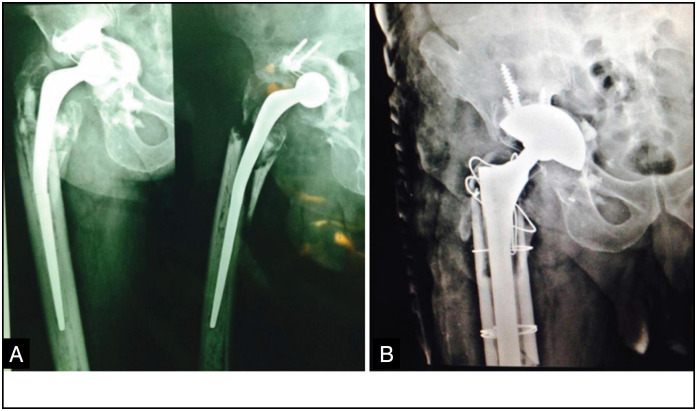

Introduction: Pelvic dissociation is a complex condition with a high rate of surgical complications and no established standard treatment. Surgery aims to preserve limb function by restoring bone structure and hip biomechanics. Conventional orthopaedic implants are made from materials such as stainless steel, cobalt-chrome or titanium. High-porosity implants have been introduced to improve the durability of hip arthroplasty.

Method: A descriptive observational study carried out at the Hospital das Clínicas of the Federal University of Goiás and at the Orthopedics and Traumatology Clinic (COT) in Goiânia. Data was collected from the medical records of patients who underwent total hip arthroplasty between 2012 and 2020, using titanium or tantalum implants, both high-porosity materials.

Results: The study included 26 patients, 53.8% female and 46.2% male. The majority (34.6%) were aged between 60 and 69. Of the patients, 53.8% used titanium implants and 46.2% tantalum. After surgery, 38.5% had a Harris Hip Score between 70 and 80, with 61.5% of patients showing osseointegration in less than six months.

Conclusion: Tantalum, due to its high porosity, was effective in treating patients with pelvic dissociation undergoing revision total hip arthroplasty. Level Of Evidence lV; Descriptive Observational Study .